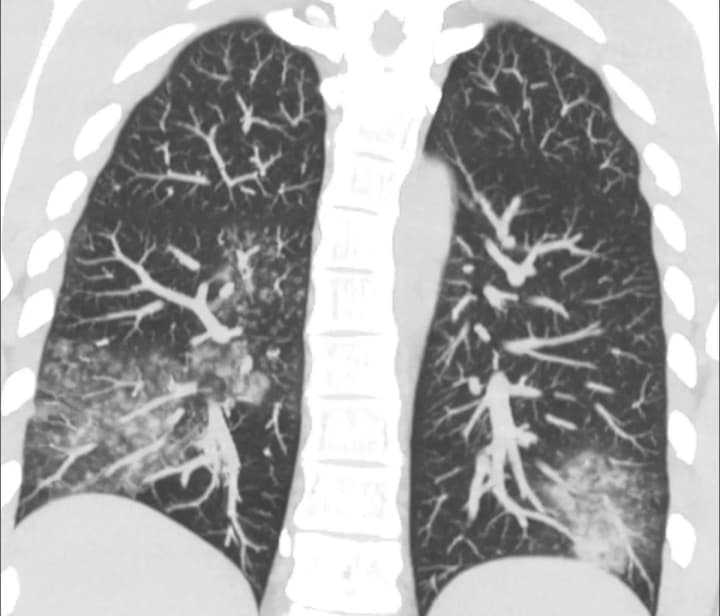

Согласно данным Центра общественного здоровья, в Украине с начала сезона зарегистрировано 13 подтвержденных случаев заражения, хотя реальное количество может быть выше. Заражение происходит капельным путем, а инкубационный период длится от 3 до 6 дней. Заболевание может быть как легким, так и тяжелым, иногда приводит к развитию фульминантной дыхательной недостаточности, особенно у людей с ослабленным иммунитетом.

Особое внимание следует уделять людям, которые находятся в группе риска, и своевременно диагностировать заболевания. В частности, врачи рекомендуют измерять уровень сатурации крови пульсоксиметром, чтобы своевременно выявить признаки дыхательной недостаточности.